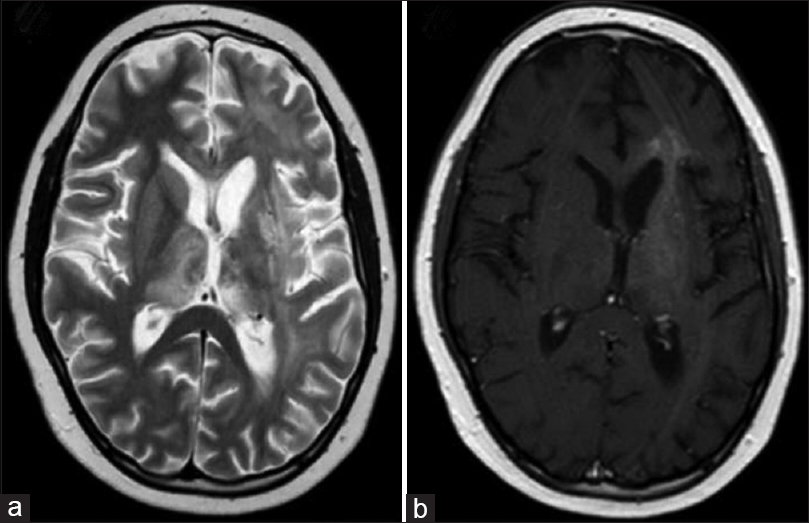

男孩的神经系统检查显示右核上面神经麻痹,上肢近端2级和远端3级,左上肢4级;反射清晰对称,左右两侧有巴宾斯基征。血液和脑脊液检查正常。MRI显示双侧丘脑、基底核和白质弥漫性病变,T1和T2加权像呈高信号,无增强。光谱显示有胆碱峰。患者接受了左顶骨钻孔立体定向活检,无并发症。病理分析显示他患有WHO 3级星形细胞瘤,免疫组化显示胶质纤维酸性蛋白阳性,增殖指数为20%。患者开始接受替莫唑胺化疗并伴随放疗(60戈瑞),可惜的是,30天后,新的核磁共振成像显示病变进一步增长,神经系统逐渐恶化,其父母决定在放疗结束前停止治疗。

图:T2加权像(a)高强度增强,T1加权像(b)显示对比度增强